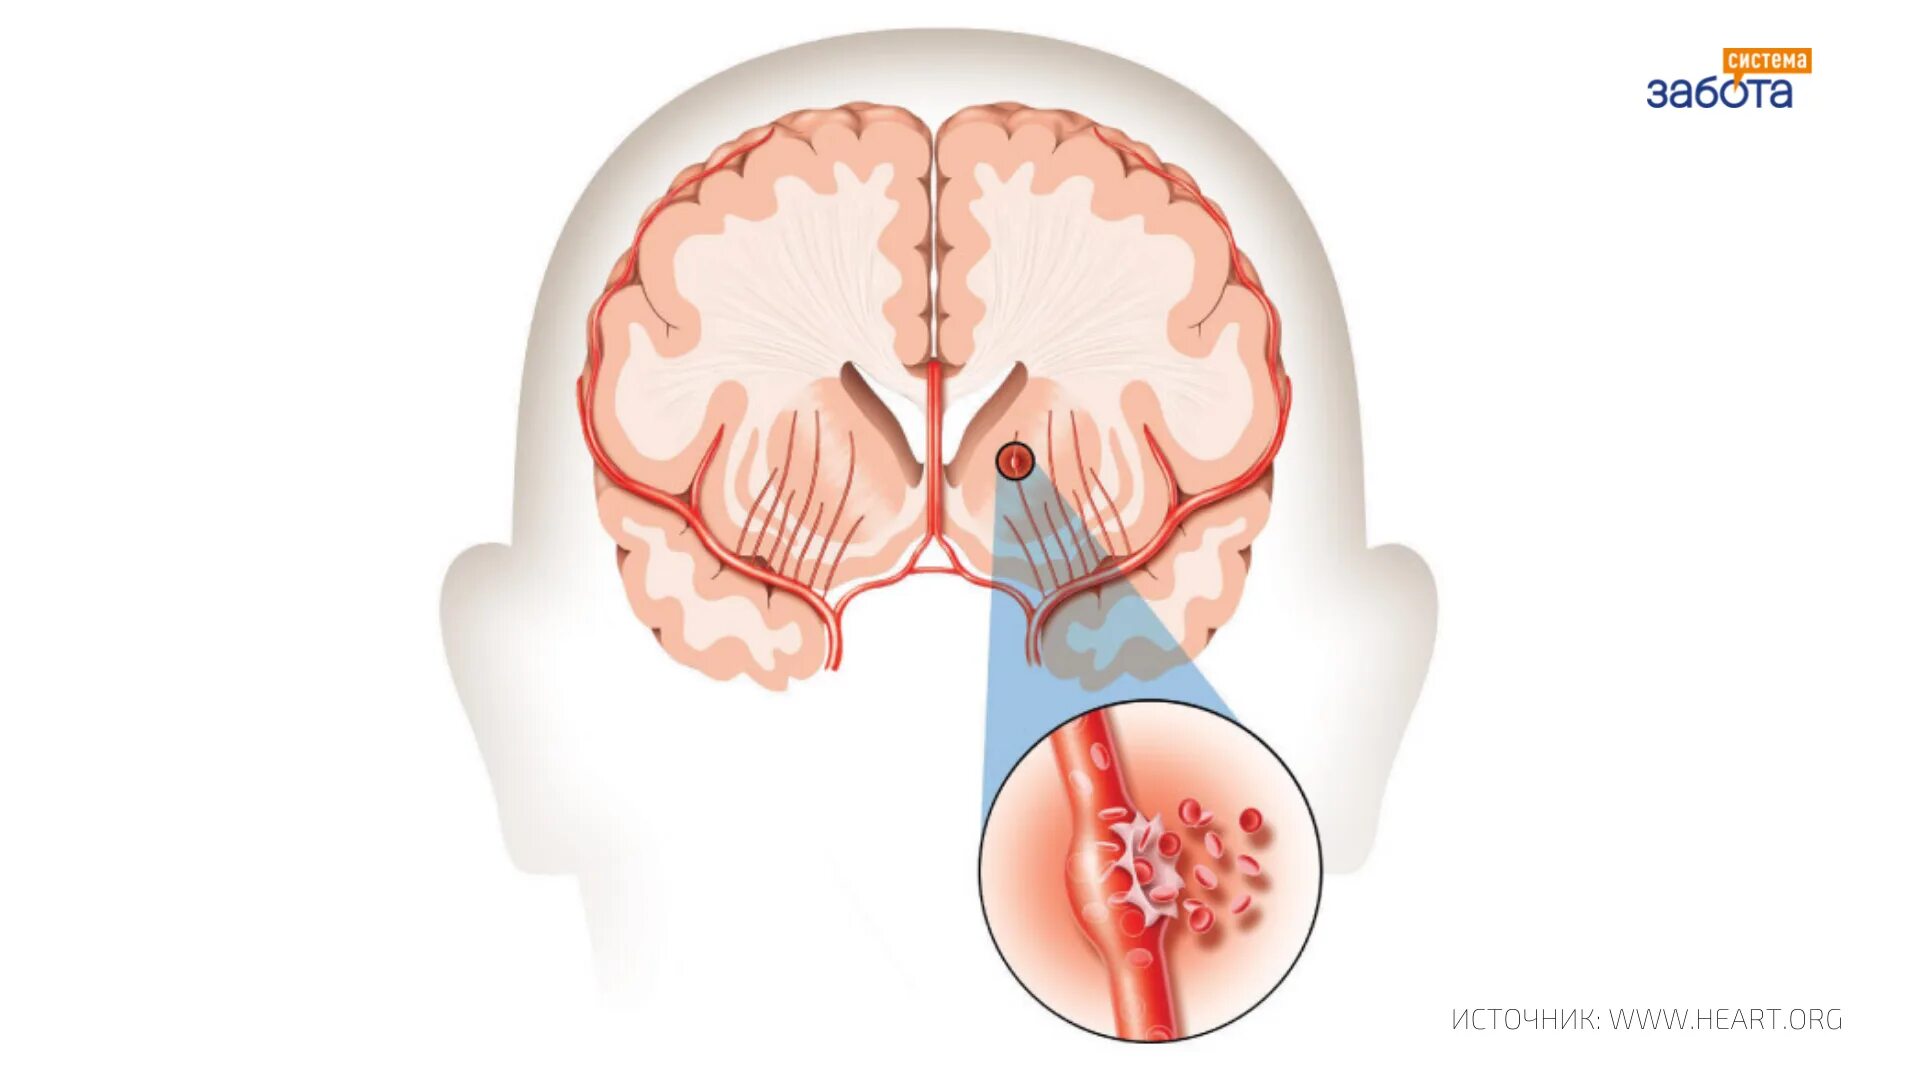

Ишемическом инсульте кровоизлияние